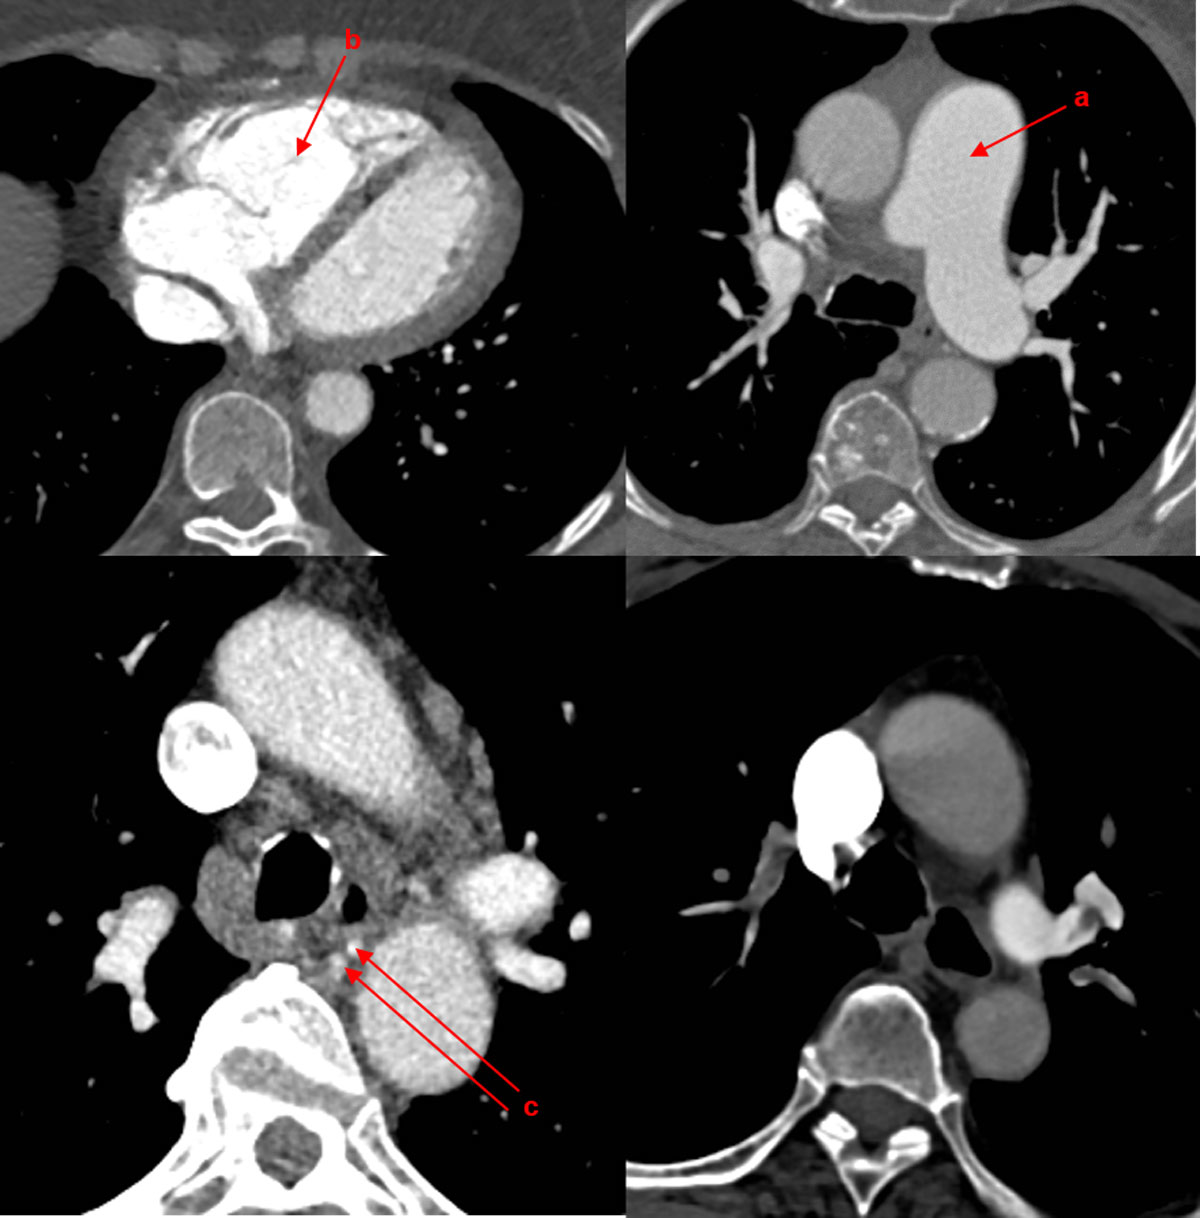

Typical local vascular characteristics on CT (fig. 8) are:

Figure 8 Local vascular characteristics on computed tomography. (a) Partial filling defects, mostly eccentric; (b) organised embolism; (c) intravascular bands and webs; (d) poststenotic dilatation. (Courtesy of Prof. T. Frauenfelder.)

Typical systemic vascular characteristics on CT (fig. 9) are:

Figure 9 Systemic vascular characteristics on computed tomography. (a) Enlargement of central pulmonary vessels; (b) enlargement and hypertrophy of right ventricle; (c) enlargement of bronchial arteries. (Courtesy of Prof. T. Frauenfelder.)

Furthermore, typical parenchymal characteristics on CT (fig. 10) are:

Figure 10 Parenchymal characteristics on computed tomography. (a) Mosaic pattern; (b) pulmonary infarctions; (c) bronchial dilatation / ipsilateral bronchiectasis. (Courtesy of Prof. T. Frauenfelder.)

The introduction of dual-energy CT (DECT) (fig. 11) permits functional data on lung perfusion (iodine distribution maps / lung perfusion blood volume images) in addition to anatomical images [58]. With the processed data, the following images can be generated: conventional grey-scale images, colour-coded overlays that highlight the iodine distribution, and virtual nonenhanced images from post-contrast images by use of iodine-subtraction techniques [43]. These are reader-independent and rapid tools to quantitatively assess regional iodine density, reflecting pulmonary perfusion, and correlate with a V/Q scan or single photon emission computed tomography (SPECT) V/Q scan [62, 63]. Qualitative assessment of less- or under-perfused lung areas is comparable to scintigraphy [43, 64, 65], and might replace V/Q scans in the future.

Figure 11 Dual-energy computed tomography (CT). (a) Contrast-enhanced CT axial reconstruction demonstrating a dilated right atrium, and narrowing of the pulmonary arteries of the right side by thromboembolic material; (b) contrast-enhanced CT coronary reconstruction with mosaic perfusion pattern; (c) dual-energy CT scan showing iodine mapping of unmatched perfusion defects. (Courtesy of Prof. T. Frauenfelder.)